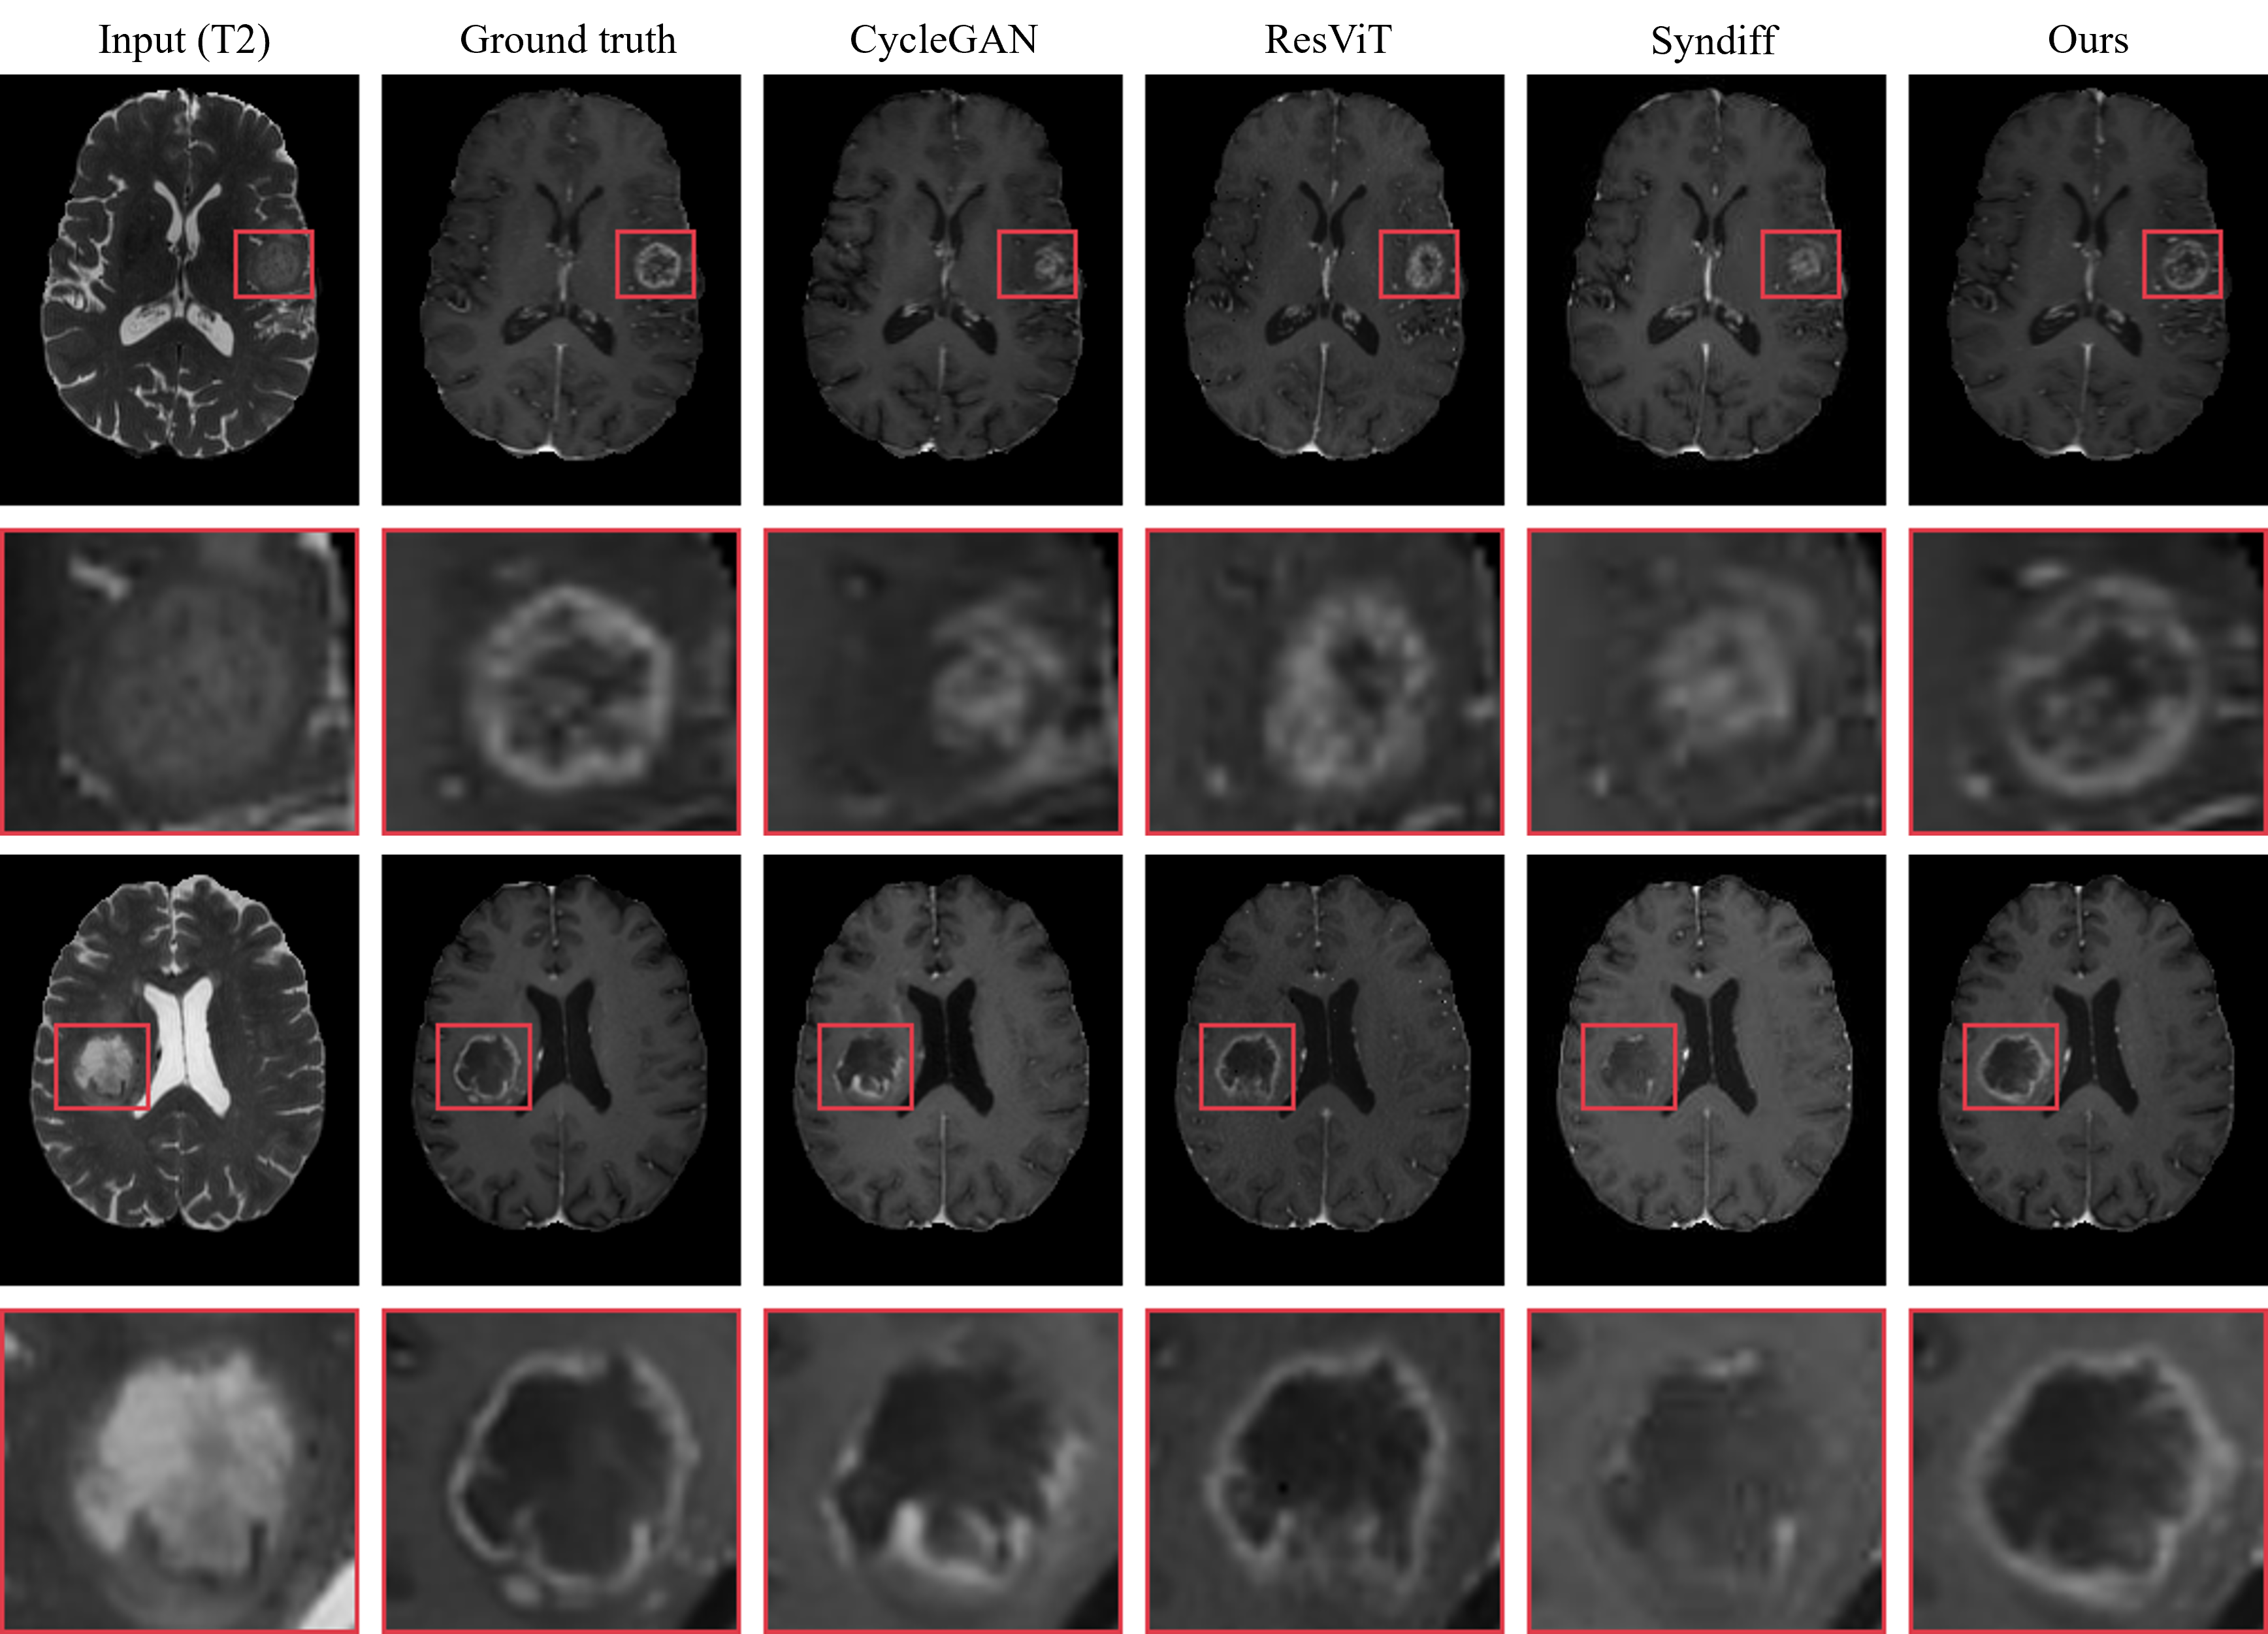

Figure 3: Visual comparison of synthesis results from all one-to-one models on the BraTS 2021 dataset. Each model takes T2 as inputs simultaneously to synthesize T1ce.

Fig. 2 and Fig. 3 show a comparison of the generated results between our method and CycleGAN, ResViT, and SynDiff in the single-input scenario. Clearly, our method synthesizes the most realistic details, with fewer artifacts and clearer tumor contours, which are critical for accurate diagnosis. While there is little difference in the healthy tissue synthesis across the different methods, our model outperforms the competing methods when it comes to lesion areas. It is noteworthy that during the testing phase, we did not use any prompts, yet our model still demonstrated strong attention to abnormal regions. Specifically, when only T1-weighted is used as input, as shown in the second-row example of Fig. 2, only our method does not miss small lesions. When T2-weighted is used as input, due to the more prominent lesions on the T2 image, as shown in Fig. 3, all methods do not miss any lesions. However, our model still achieves the most perfect detail synthesis and clear tumor contours, demonstrating significant advantages when handling lesions of different sizes.